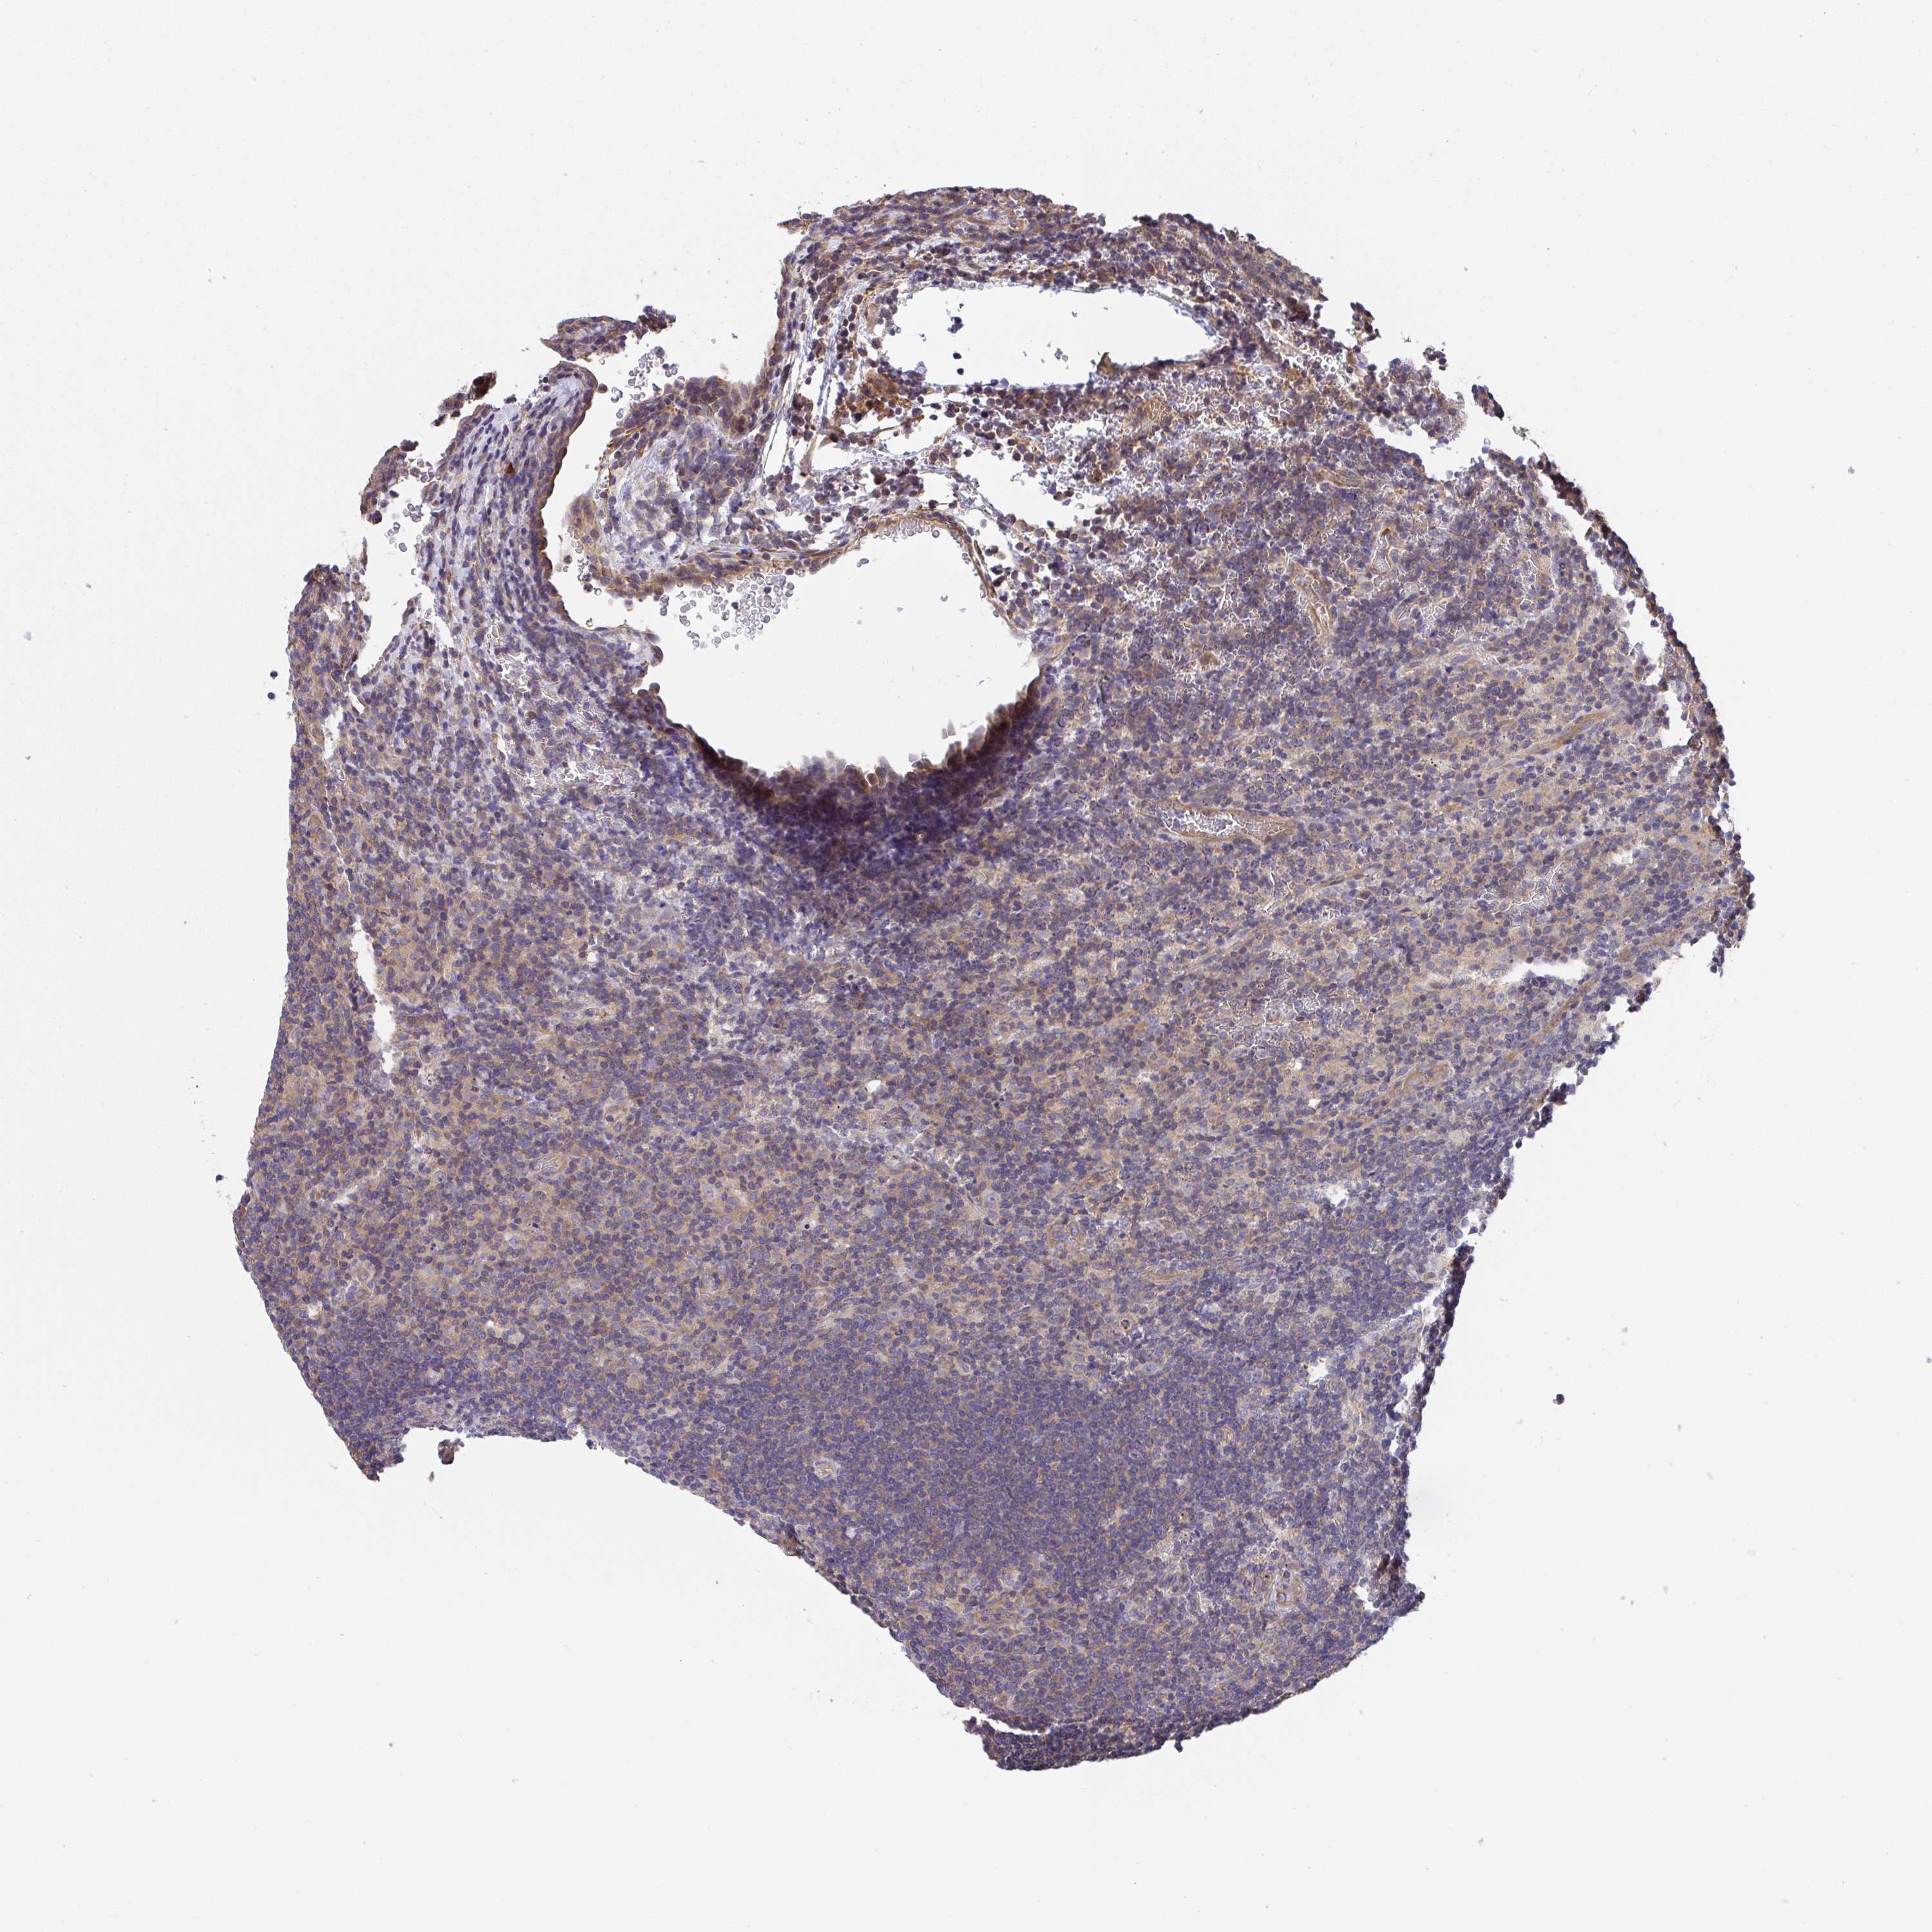

CANCER LYMPHOMA Show tissue menu

LYMPHOMA - Protein expressioni

A mouse-over function shows sample information and annotation data. Click on an image to view it in a full screen mode. Samples can be filtered based on level of antibody staining by selecting one or several of the following categories: high, medium, low and not detected. The assay and annotation is described here.

Each image is clickable and will lead to virtual microscopy that enables deeper exploration of all samples and also displays staining intensity scores, fraction scores and subcellular localization as well as patient and tissue information for each sample.

Antibody HPA057855

Staining

High

Medium

Low

Not detected

Intensity

Strong

Moderate

Weak

Negative

Quantity

>75%

75%-25%

<25%

None

Location

Nuclear

Cytoplasmic/membranous

Cytoplasmic/membranous,nuclear

Malignant lymphoma, non-Hodgkin's type, Low grade

Malignant lymphoma, non-Hodgkin's type, High grade

Hodgkin's disease, NOS